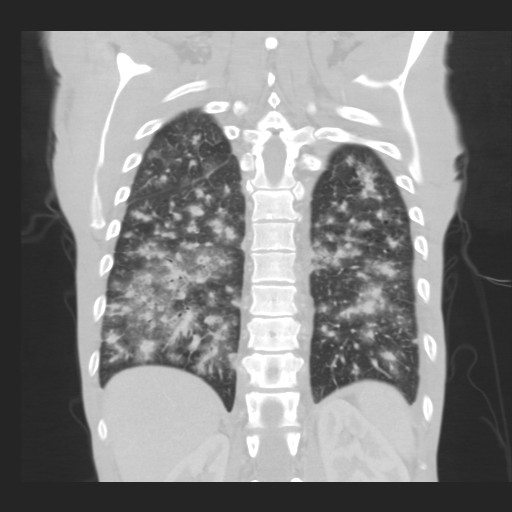

Gallery Lung Cancer Miscell KS cor 2

KS cor 2